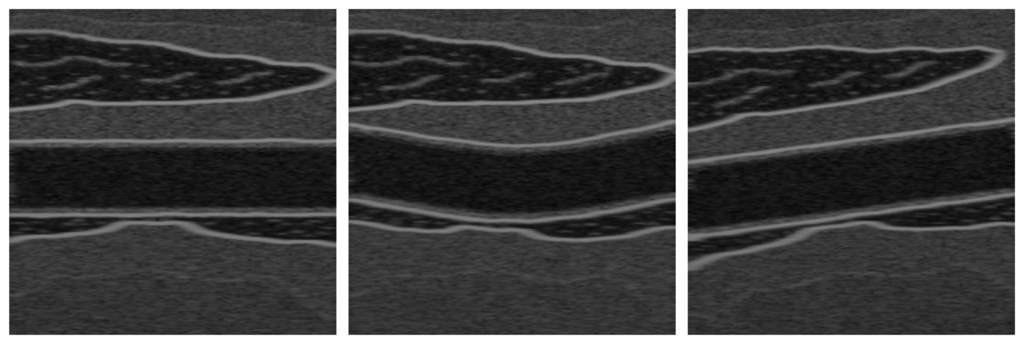

To evaluate the proposed methods, the Field II Ultrasound MATLAB library [34] was used to generate nine sequences simulating the wall displacement of the common carotid artery. Each sequence involves a complete cycle of the cardiac system with a frequency of 25 Hz per cycle. These simulations were generated with 1024 physical elements, a transducer center frequency of 5 MHz, 100 MHz of sampling frequency, and 64 active elements. The sequences are based on three different topologies as shown in Figure 1, where diverse amplitudes of motion are used, as explained later in this section. Although these synthetic images are clearer than real US artery images, having the ground-truth motion allows quantitative evaluation metrics to compare different methods. We include also the simulation parameters used to produce these synthetic sequences (Table 1) to facilitate the reproduction of our results.